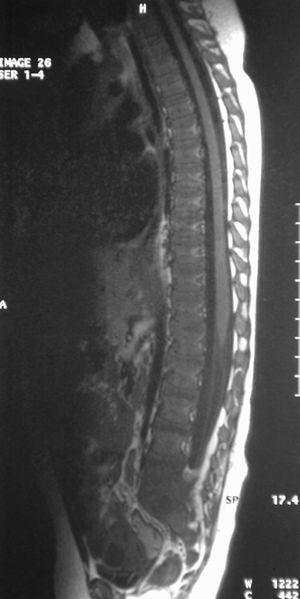

El hemograma, los tiempos de coagulación y la proteína C reactiva fueron normales. La velocidad de sedimentación globular (VSG) de 42 mm/h, indicaba un probable proceso inflamatorio. En la radiografía de columna vertebral se observó una mala definición de los platillos vertebrales inferior de L5 y superior de S1, con aparente esclerosis (fig. 1). La gammagrafía con 99mTc mostró un aumento de captación leve, de morfología lineal, en área teórica de las carillas articulares de cuerpos vertebrales L5-S1 (fig. 2).

Figura 1. Radiografía de columna vertebral, se observa esclerosis de platillos vertebrales inferior L5 y superior S1 y disminución del espacio discal.